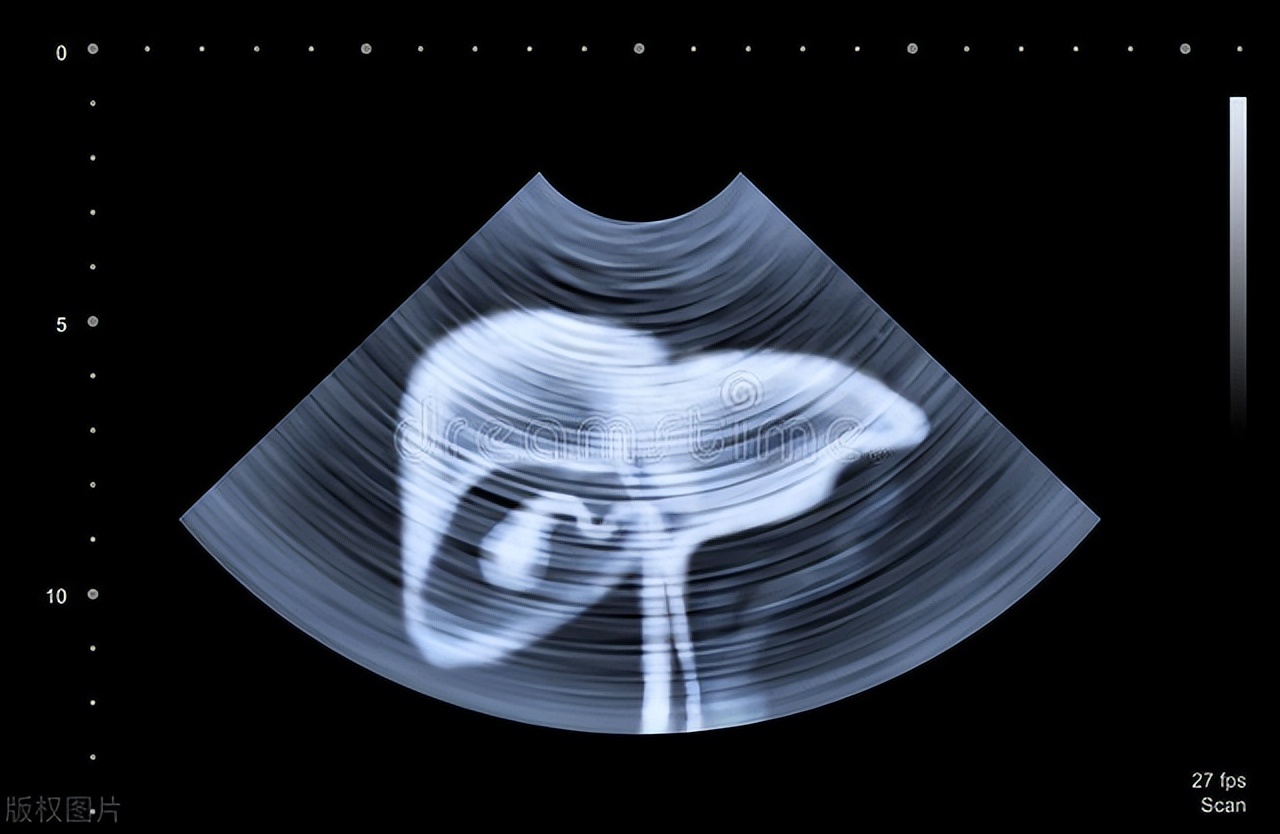

1、肝脏超声检查

肝脏超声检查安全实惠、可重复,无辐射。通过此检查能了解肿瘤大小和形态,知道肿瘤生长的位置,诊断准确率能达到9成以上,而且也能诊断多种肝脏病变。